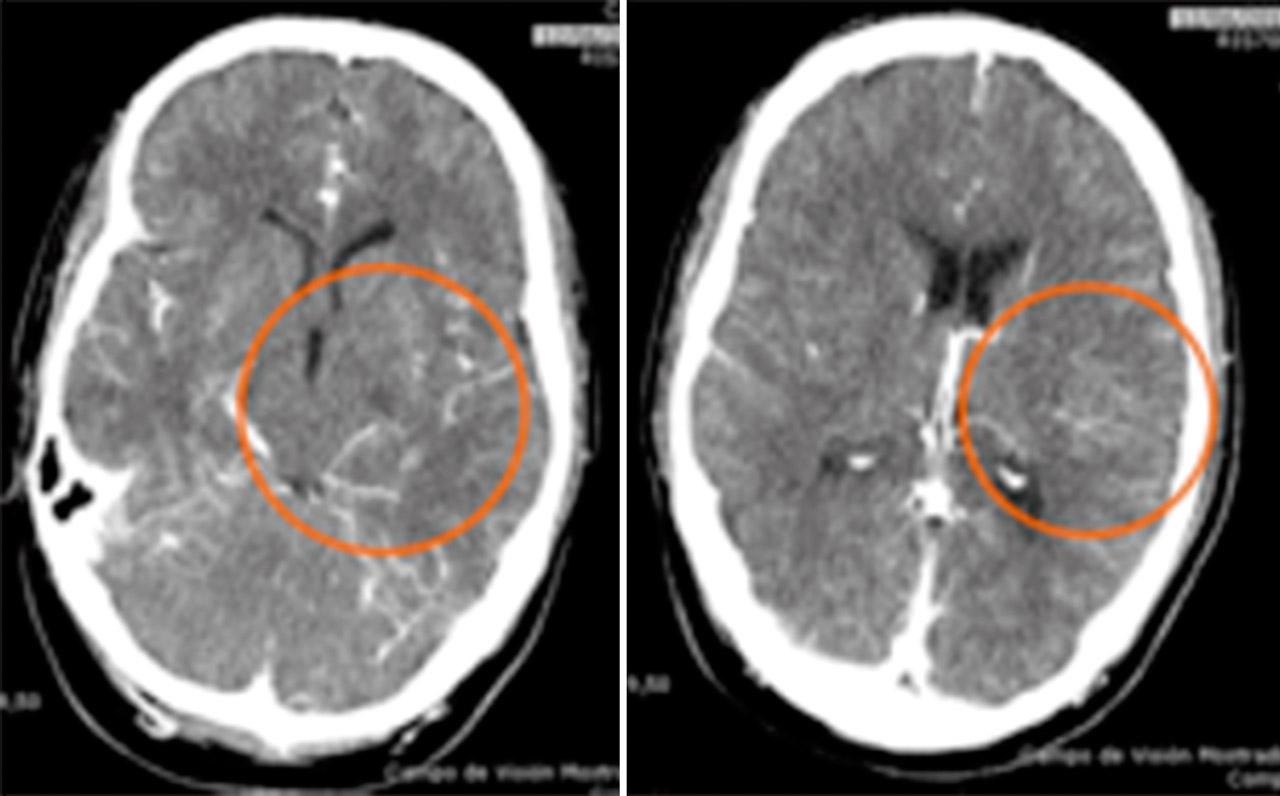

Se procedió a la desintubación, objetivando agitación y alteración para la emisión y comprensión del lenguaje. Ante la sospecha de un accidente cerebrovascular se realizó una tomografía computarizada (TC) craneal multimodal objetivando un aumento en los tiempos de tránsito medio, tiempo pico y del flujo sanguíneo, sin alteraciones en el volumen cerebral, compatibles con área de penumbra isquémica del 100%. En angio-TC, se evidenció un defecto de repleción en la arteria cerebral media izquierda, segmento M1, de 12,5 mm (Figura 6). Ante estos hallazgos, se inició el tratamiento trombolítico, 2 horas después de verle asintomático por última vez. A pesar de la mejoría progresiva, se decidió realizar una arteriografía para valorar la extensión del defecto, viendo una imagen arteriográfica compatible con oclusión crónica de M1 izquierda, sustituida por múltiples colaterales, dando el aspecto de Moyamoya (Figura 7).

Ingresó en la Unidad de Ictus 5 horas después, donde se efectuaron estudios diagnósticos. En una nueva TC multimodal persistía el defecto de repleción de M1 izquierda y múltiples vasos colaterales; diagnosticándose de síndrome de pseudo-Moyamoya.